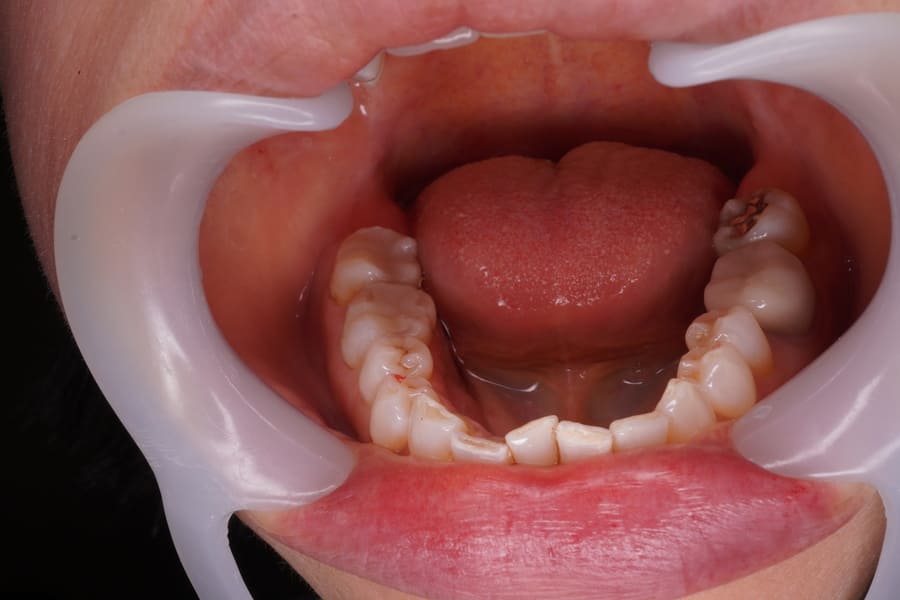

右下奥歯2本のメタルインレーを除去しモノリシックジルコニアインレーで修復した症例 ・ 右下6,7番をモノリシックジルコニアインレーで修復し審美的および機能的改善を行ったケース

術前(2025年12月)

| 治療内容 | 下顎右側6,7番にメタルインレーが装着されている。まず見た目を治したい。 出来るだけ体に害のない材料で治したい。 右下6,7番既存のメタルインレーは咬合面から頬側に及ぶ窩洞であった。 縦溝の存在とブラキシズムがあり夜間ナイトガードを装着している。 破折予防に重点を置き審美性重視のポーセレンe-maxではなく、強度重視のモノリシックジルコニアインレーで製作することとした。 シェード選択で頬側面上方と下方で色調が異なり、さらに咬合面の色調も異なるものであった。 患者さんの一番の訴えであり一番目立つ頬側の縦溝の色調を残存歯質頬側咬合面よりの色調と調和させた。 残存資質との色調をより調和させるために、レジンセメントの色調を2種類トライアルした。 レジンセメントはパナピアV5、セメントカラーはユニバーサルカラーを選択した。 ラバーダム防湿を行い右下6,7番の試適を行った。 適合に問題ないため、合着操作に移行した。 セラミック内面にサンドブラスト処理とセラミックプライマーを塗布した。 歯質の窩洞にはティースプライマーを塗布し20秒後にエアー処理した。 その後、パナピアVユニバーサルカラーで合着した。 Tack Cure(タックキュア)を併用してセメント除去を行った。 硬化後、単探やデンタルフロスを用い余剰セメントを除去した。 その後、ビトリファイドダイヤを用いマージンのすり合わせと咬合調整を行い、グロスマスターZR、ジルグロスで研磨を行った。 この際、研磨が非常に重要となります。 研磨が不十分であれば、非常に硬いジルコニアの場合、相手方の歯を簡単に減らしてしまいます。 形態の違う研磨器具を巧みに使い分けることで仕上げをしていきます。 合着後、咬合診査を行い合着時の誤差を確認し僅かな調整が必要であったため再度、調整、形態修正、研磨を行った。 合着1週間後に各種チェックを行った。 僅かに咬合調整の必要があり、調整、研磨を十分慎重に行い鏡面研磨を行い終了した。 |